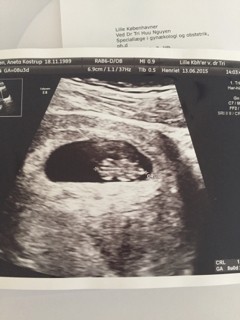

Miedzy 22-25 mam zrobig genetyczne ale nie normalne tylko echo tetna plodu a normalbe normalnie ok 20 jesli dobrze pamietam. I pozniej ok 30